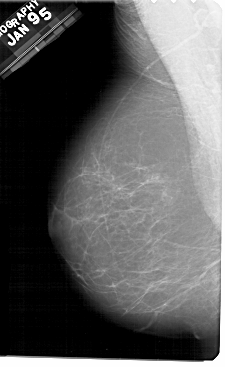

A_1943_1.RIGHT_CC

RIGHT_CC LINES 5491 PIXELS_PER_LINE 3001 BITS_PER_PIXEL 12 RESOLUTION 43.5 OVERLAY